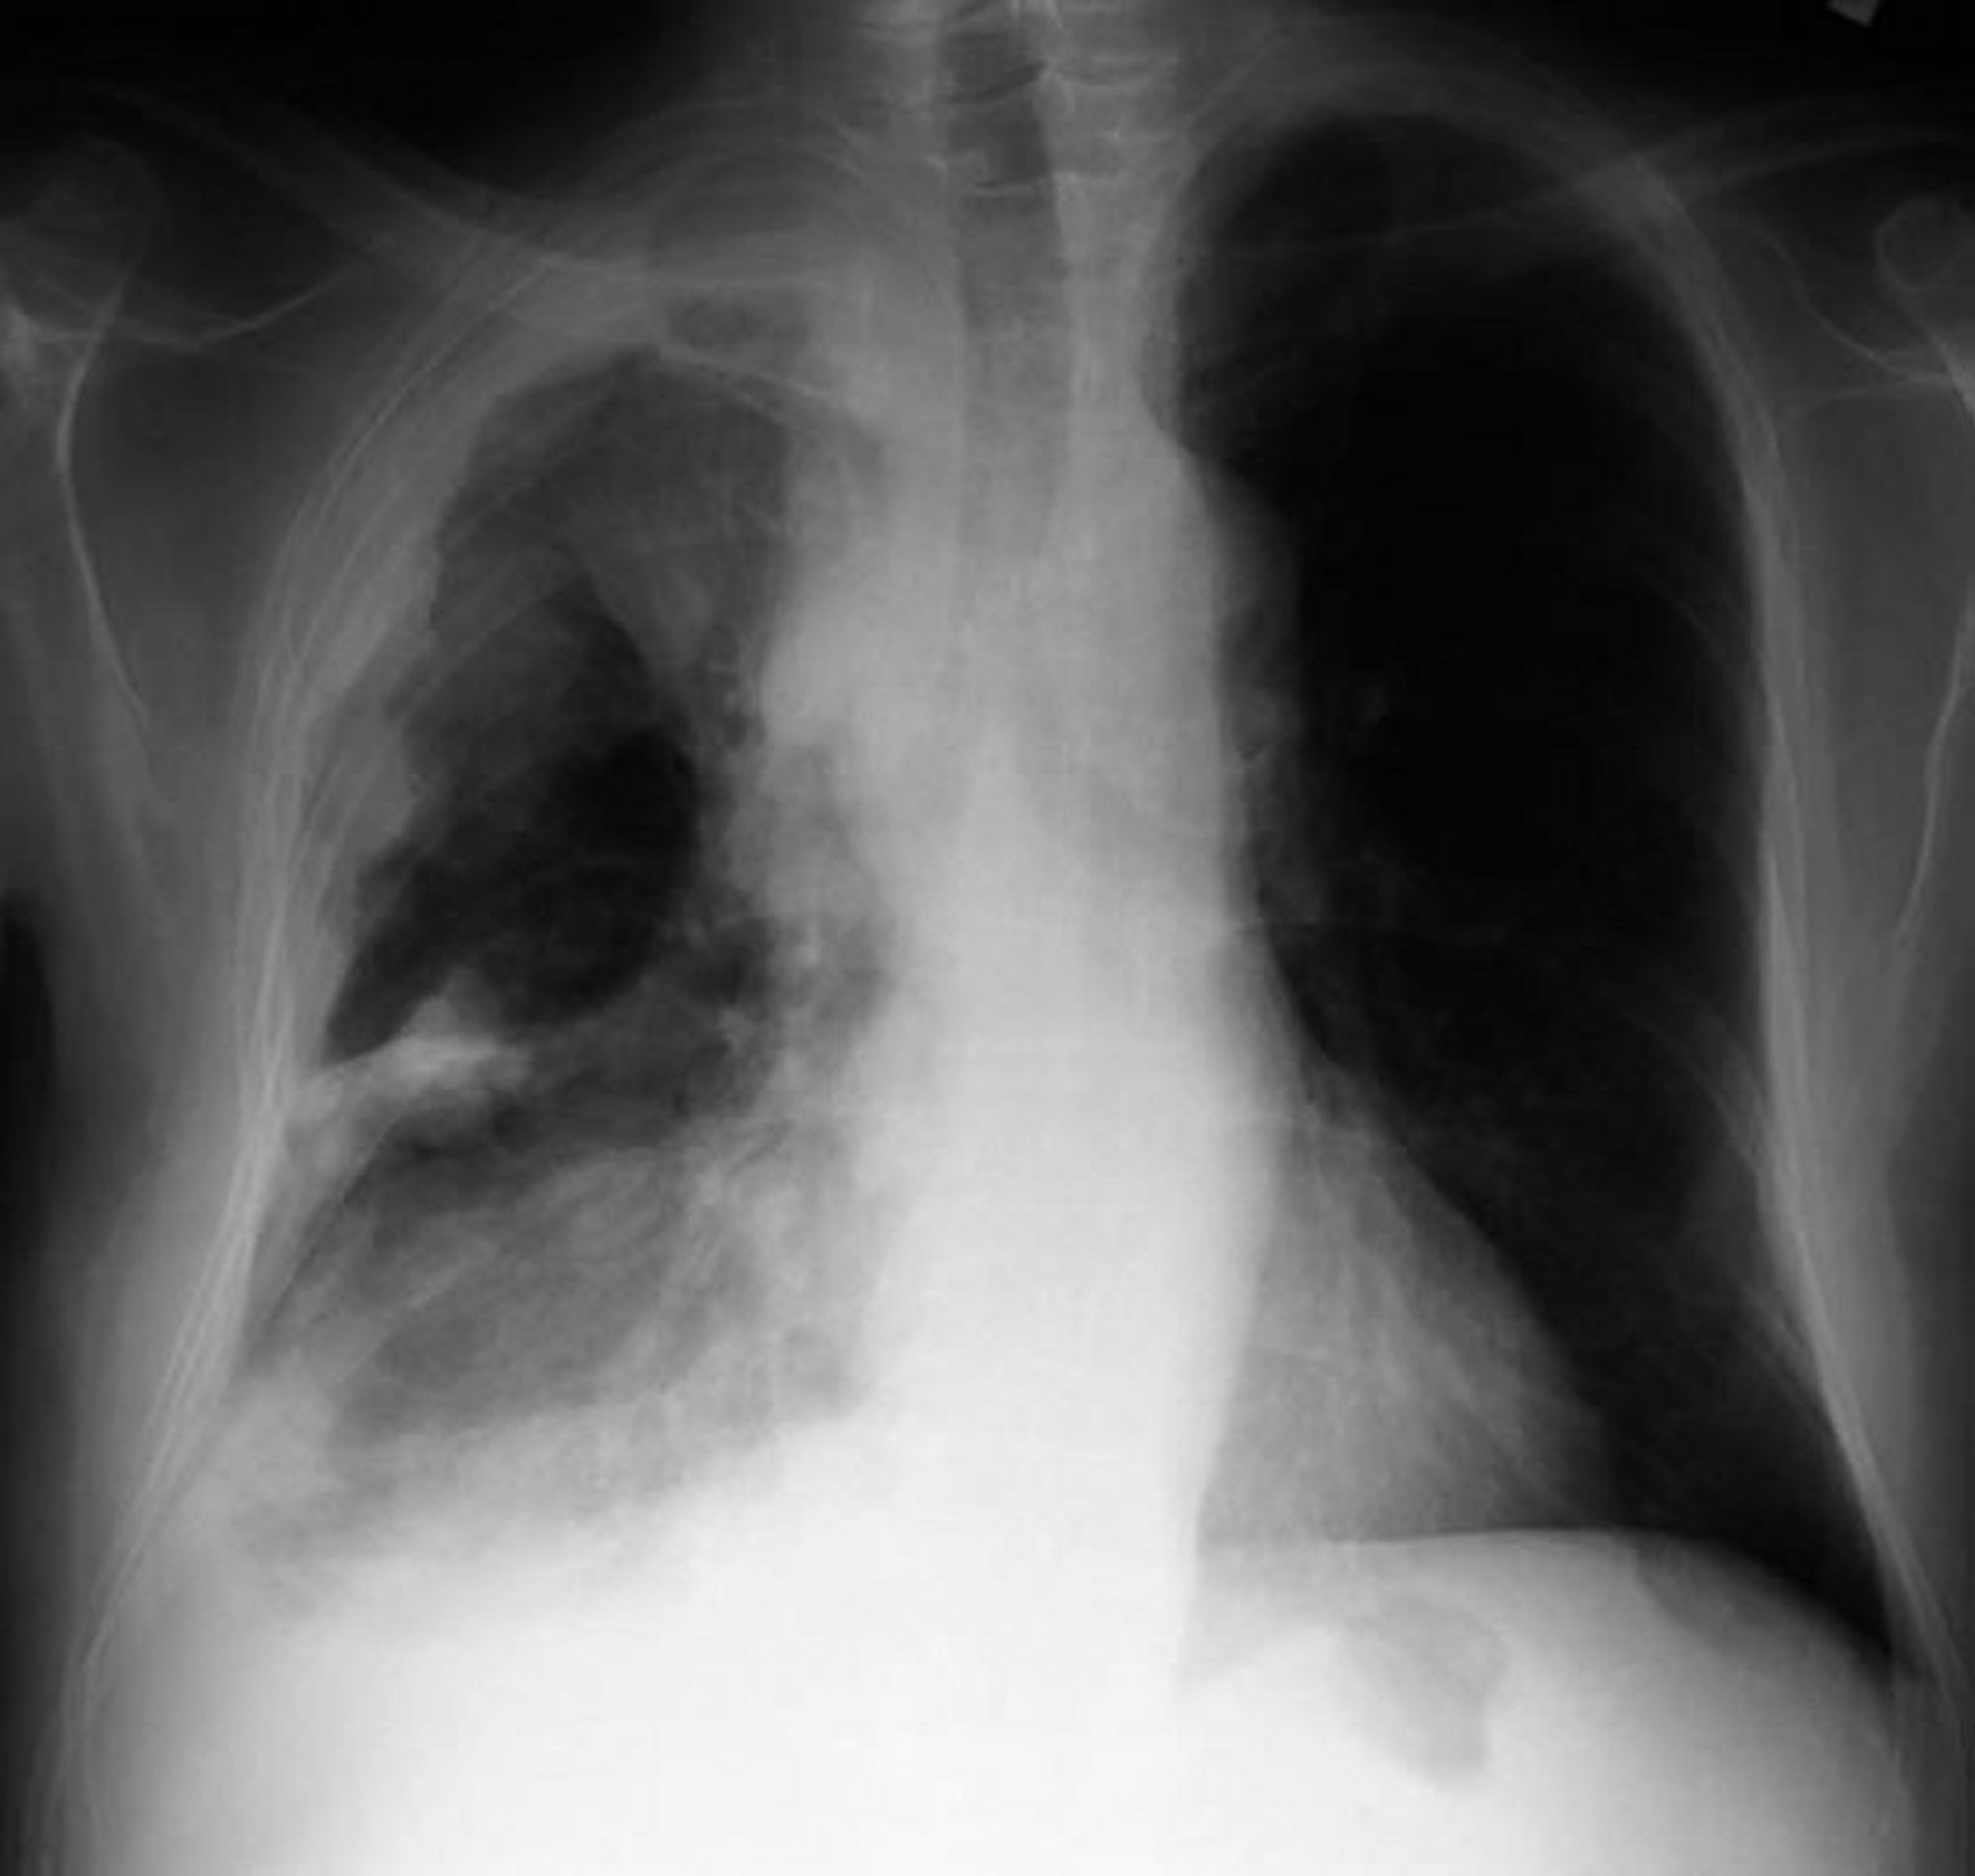

Mesotelioma pleurico

La RX torace in un paziente con mesotelioma pleurico mostra ispessimento pleurico con masse nodulari sulla pleura parietale.

By permission of the publisher. From Huggins J, Sahn S. In Bone's Atlas of Pulmonary and Critical Care Medicine. Edited by J Crapo. Philadelphia, Current Medicine, 2005.